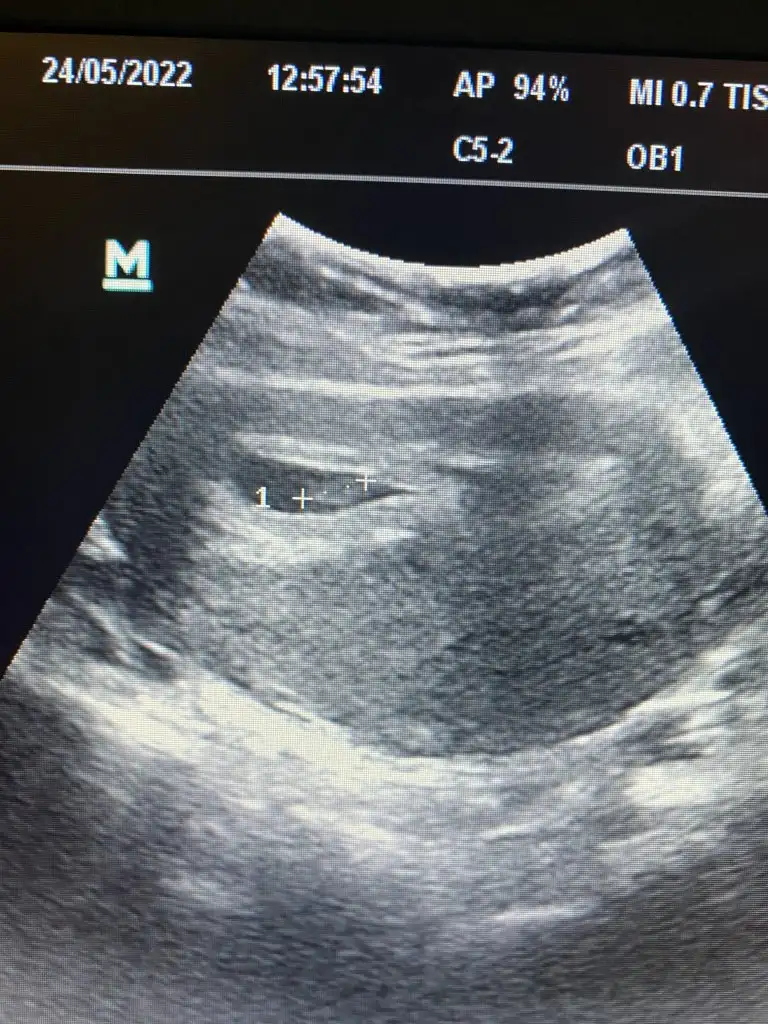

Canım erkek bu buyuk ihtimalle rabbim gönlünüze gore versin cinsiyet belli olunca yazmayi unutmaMerhaba benim için de tahminde bulunabilir misinizultrason ölçüsüne göre 5+6 vajinal bakıldı

Ama ne yazık ki ramzi teorisi ikiz gebelik için geçerli değulilYok bu yöntemi çürüten çok kişi gördüm ...ama ramzi teorisinde hiç şaşmadım sadece plesantaya göre yorum yapiliyo plesanta şu kesedeki beyaz parlak alankarından ultrasonda plesanta solda ise erkek sağda ise kiz oluyo .vajinal usg de ise tam tersi oluyo

Kuzum kıza benzettim ama pek emin değilim plesanta sağda gibi duruyo ama çok net değilBizde karından 7 haftalığız bende tahmin alabilir miyimEki Görüntüle 3072981